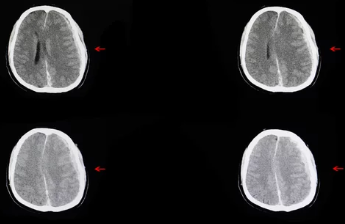

뇌출혈이 의심되는 경우, 즉시 의료 기관을 방문하여 정밀 진단을 받는 것이 중요합니다. 컴퓨터 단층촬영(CT)이나 자기공명영상(MRI) 검사를 통해 뇌 내부의 출혈 여부를 확인할 수 있으며, 필요한 경우 적절한 치료를 받을 수 있습니다.